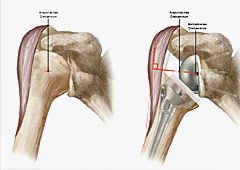

Im Falle einer Arthrose ist der Knorpel

des Oberarmkopfes abgenutzt.

Nach Implantation eines künstlichen Gelenkes

Mehrfragmentfraktur des Oberarmkopfes

Ausheilungsergebnis mit einer schweren Schultergelenksarthrose

Nach Implantation einer Schultergelenksprothese

Links: Abbildung einer Defektarthropathie, der Oberarmkopf wandert nach oben unter das Schulterdach.

Rechts: Durch die Umkehrung des Kopf-/Pfannenprinzips kann der Oberarmkopf unten gehalten werden, so dass andere Muskeln (Delta-Muskel) die Funktion übernehmen können.

Schematische Darstellung der Implantate

Nach Implantation